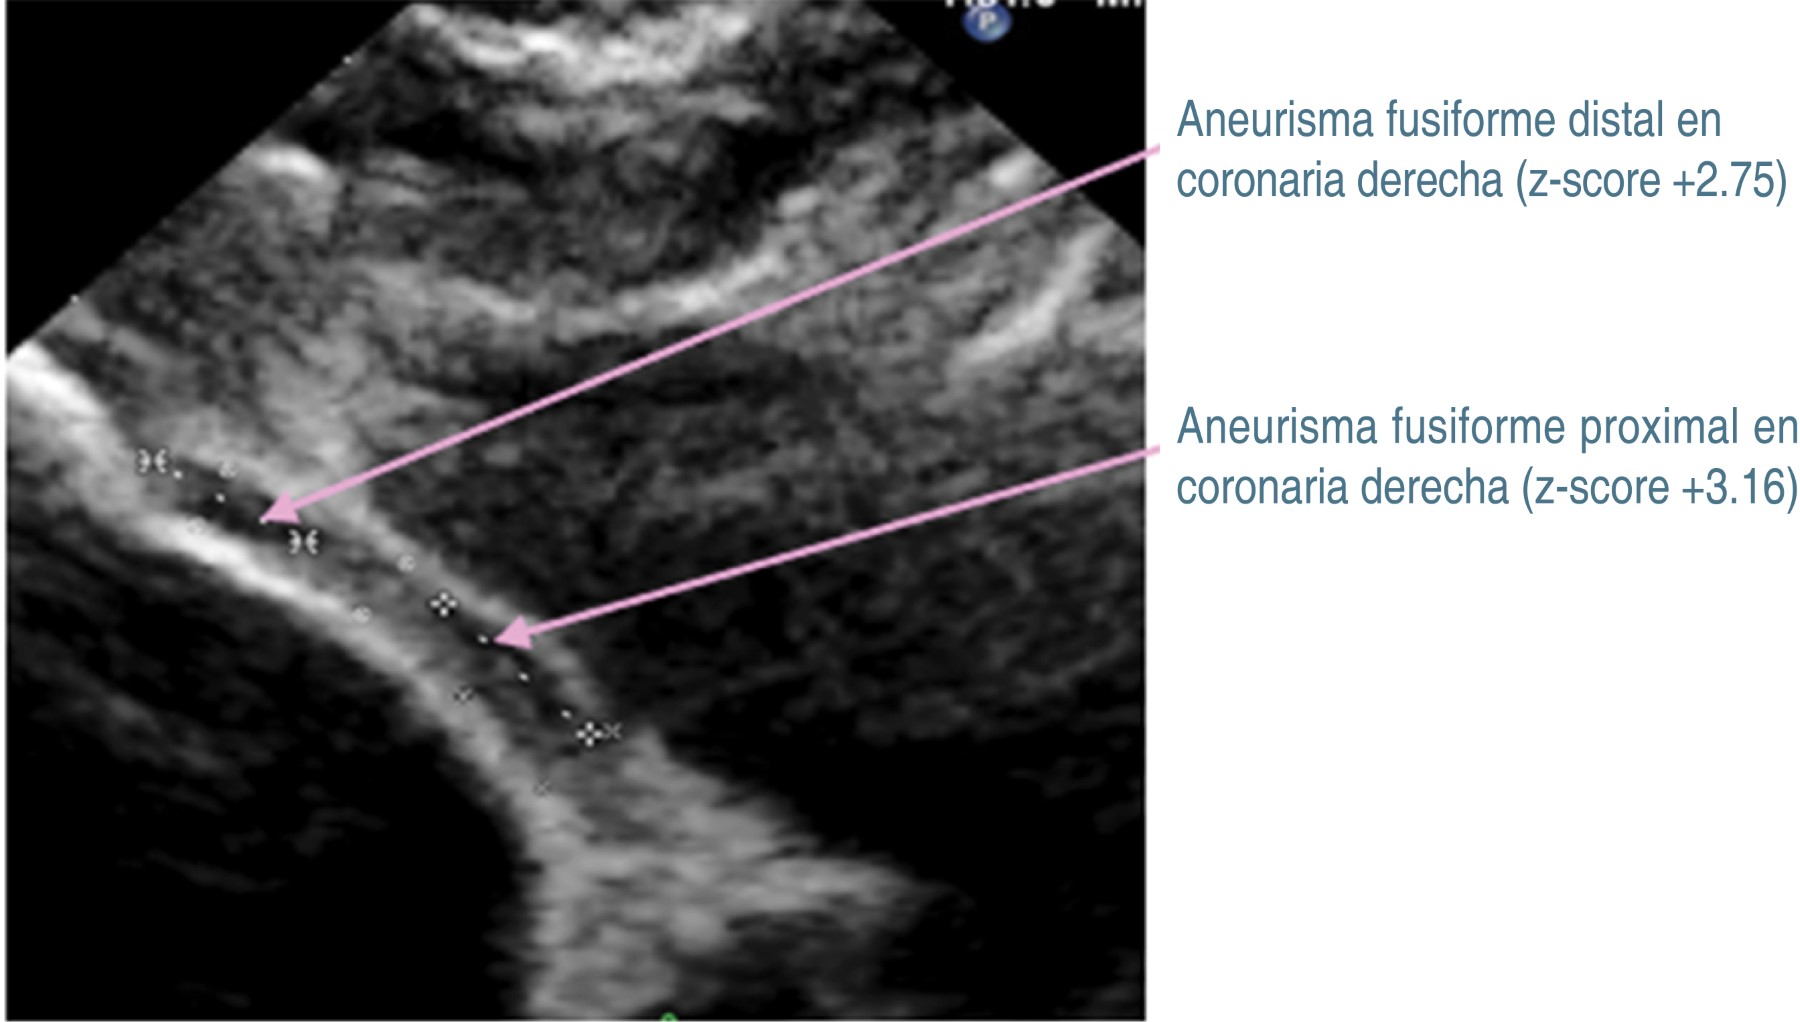

Los datos previos orientaron a que se trataba de EK, por lo que se inicia inmunoglobulina intravenosa (IGIV) humana a dosis de 2 g/kg/día, ácido acetilsalicílico (ASA) a dosis de 80 mg/kg/día, clopidogrel (0.5 mg/kg/día) y enoxaparina (1 mg/kg/dosis). La fiebre cede en las primeras 24 horas, presentando mejoría del estado general. Cinco días después, en ECT de control, el tronco coronario izquierdo medía 3.9 mm (z-score +7.05), sin evidencia de trombo en su interior. Mientras que en la coronaria derecha hay regresión de aneurismas fusiformes a aneurismas pequeños, midiendo 2.4 × 5.4 mm en porción proximal (z-score + 3.16), y de 1.9 × 4.5 mm en porción distal (z-score + 2.75) (Figura 3). En el tronco coronario izquierdo medía de 3.9 (z-score + 7.05), sin evidencia de trombo (Figura 4).

Figura 1

Figura 3